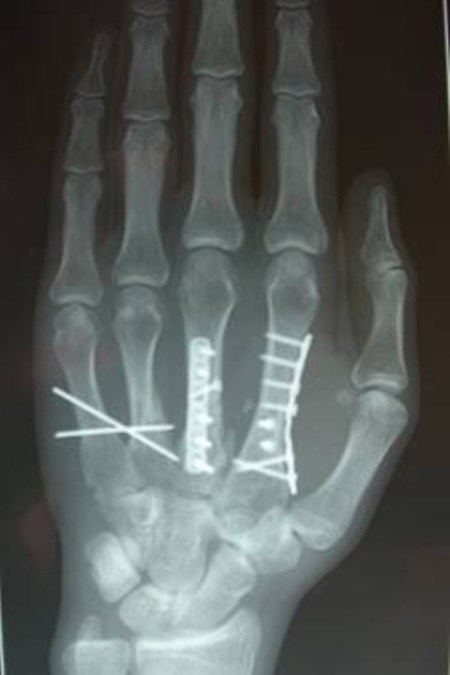

= fracturen van middenhandsbeentjes en vingerfracturen

Is de breuk niet stabiel genoeg of teveel verplaatst om tot een goede heling te komen is operatief ingrijpen noodzakelijk, dit kan gebeuren door plaat osteosynthese, pinfixatie of uitwendige fixatie.